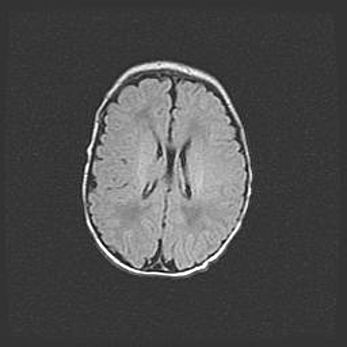

Открытая гидроцефалия.

Возраст: 9 месяцев 12 дней

Вес: 6800 г

Пол: мужской

Окружность головы: 41,5 см

Срок гестации: 28 недель

Гидроцефалия головного мозга у новорожденных имеет характерный признак: опережающий рост окружности головы приводит к визуально хорошо определяемой гидроцефальной форме сильно увеличенного в объёме черепа. Детские неврологи определяют следующие симптомы гидроцефалии у грудничков: выбухающий напряжённый родничок, частое запрокидывание головы, смещение глазных яблок к низу.